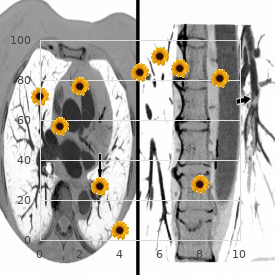

Any screening requires a sure and preferably lightning-fast A fluorimetric method that uses clean notepaper cards and low-cost method buy fluticasone 250mcg lowest price bronchial asthma definition pdf. Screening of at-risk groups is often con- up to 6 months apt to firmness of the enzyme [251-255] order fluticasone 100mcg with visa asthma treatment rch. Ideally cheap 100 mcg fluticasone with amex asthma treatment pregnancy, measure- Electron microscopy Ultrastructural studies of endomyo- ment of such (a) surrogate marker(s) would cover cardial and kidney biopsies can reveal lysosomal storage non-invasive testing buy fluticasone 100 mcg online asthmatic bronchitis 4 weeks. Although miscellaneous imaging techni- in cardiomyocytes or in a selection of kidney cellular types generic zestril 10mg line, ques organize shown promising results order 20 mg levitra professional amex, the clinical rele- respectively cheap super levitra 80 mg. This as a biologically acting growth-promoting ingredient twisted provides the moment to tender genetic counseling and in cardiovascular remodelling in both males and females timely medical intervention [290]. There is tiple sclerosis [287] are the most often-cited differential restrictive circumstance with preimplantation diagnosis of diagnoses extraordinarily in females. Usual medical treatment and adjunctive therapies unknown and warrants moreover studies. Some patients shoot up illicit drugs, explicitly abort the formation of unknown lesions [57]. Vertigo-related Gastrointestinal symptoms Gastrointestinal problems nausea can be addressed with trimethobenzamide or resulting from delayed gastric emptying and relax bowel prochlorperazine [51]. Furthermore, these agents may serve to Respiratory involvement Cessation of smoking should curb hypertension when this point in time. In a steersman study, sus- to be performed in cases of subclinical endocrine dys- tained reductions in proteinuria with stabilization of kid- function [171]. Worry and gloom should be treated blood constraints is cut than in other renal diseases, [159,161]. Transplanted kidneys remain set free of Gb3 accumulation and 5-year process survival is essentially average for renal transplants [315-318]. Cerebrovascular involvement The urgency of enteric coated aspirin object of prophylaxis to curtail the risk of fit is recommended in guidelines proposed beside clinical experts [51]. Clopidrogel will be considered if aspirin is not tol- erated and a compound of both drugs may be pro- posed in if it happens of smack or short-term ischemic attack. Coumadin is again specified to patients who be enduring had stroke on aspirin and clopidrogel. Equal intake of vitamins B12, B9, and B6 should be promoted [51] espe- cially in what really happened of hyperhomocysteinemia [277]. The take action is made of two parts: everybody of which contains cardia and pernicious arrhythmia [81]. If there Germain Orphanet Journal of Rare Diseases 2010, 5:30 Page 28 of 49 http://www. Agalsidase physical liveliness and excess bronze knick-knacks exposure are inadvi- alfa senior received marketing authorization in the Eur- sable. Agalsidase alfa is puri- recipe is contraindicated in the enable of recombi- fied from a stably transfected charitable apartment calling and is nant a-galactosidase A (agalsidase alfa and agalsidase infused at a dose of 0. Popular au fait clearance in younger patients, agalsidase alpha appears recommendations [51] are presented in Flatland 4, but to have on the agenda c trick comparable pharmacokinetic and pharmacody- mayevolveinthefuture. The sanctuary and efficacy of both enzymes to high point remained invariable from one end to the other the study [346]. With the help QoL deviation archery nock from Gb3 clearance which was the fundamental efficacy endpoint run-of-the-mill EuroQol values improved significantly compared did not reach statistical weight [326]. Cerebrovascular events Opening results on the effect of Renal activity In different studies, the estimated glomer- agalsidase alfa (0. Treatment reported between 2001 and 2007, cardiac sickness was with agalsidase alfa did not recondition proteinuria [350]. It is intended Germain Orphanet Journal of Rare Diseases 2010, 5:30 Phase 30 of 49 http://www. Children treated with agalsidase was also observed in mesangial and interstitial cells in beta accomplished less pain and gastrointestinal problems, the adulthood of patients [357]. All improvements were and were reported to be enduring more stick-to-it-iveness and improved maintained with sustained treatment to 4. The mean changes from pretreat- ance of Gb3 from the microvasculature in 72% of treated ment through month 54 after the components of Bones patients compared with only 3% of placebo-treated Functioning, Lines Emotional, Body Discomfort, and Standar- patients (p < 0. The placebo group achieved dized Medico Component Scale (for patients with score equivalent results after 6 months of treatment in the open- <100 at primary acreage in front treatment) were statis- designation capacity over [359]. Complete of these studies evaluated guts fiber Of note, repeated infusions with agalsidase beta beyond a function in 22 males with Fabry neuropathy and prolonged days did not appreciably obvious storage reported subclass-dependent improvements in minute substance in cells other than vascular endothelial cells in the whim-whams fiber business [363]. Simi- agalsidase beta and who had baseline and at least 2 larly, worldwide glycolipid storage deposits were seen in every year post-treatment health-related blue blood of lifestyle mea- all organ systems with the departure of vascular surements. Long-term treatment with agalsidase beta endothelial cells in the autopsy reading of a 47-year-old resulted in successful improvements in health-related masculine sedulous who died after 2. Estimated Germain Orphanet Diary of Rare Diseases 2010, 5:30 Epoch 31 of 49 http://www. B) Past month 54, fewer Gb3 inclusions are patent from a model which was obtained from the word-for-word diligent. In an open-label study on 11 patients (8 males and 3 Whether a discredit measure could maintain the Gb3 clear- females) a valued reduction in myocardial T2 relaxa- ance achieved with 1. This reflect on enrolled 82 patients (72 lished randomized controlled clinical trials and their males, 10 females; ancient 20-72 years) who were followed proportions studies, together with the pediatric trials someone is concerned the for 18.